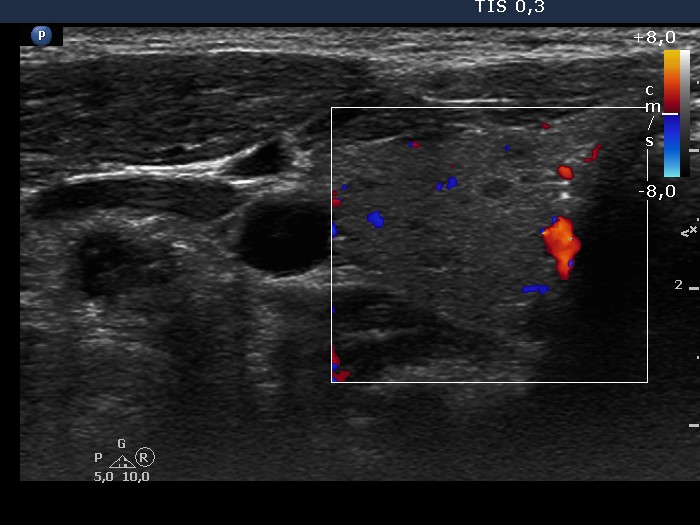

Right lobe, transverse scan, color Doppler mode. The vascularization is not specific.